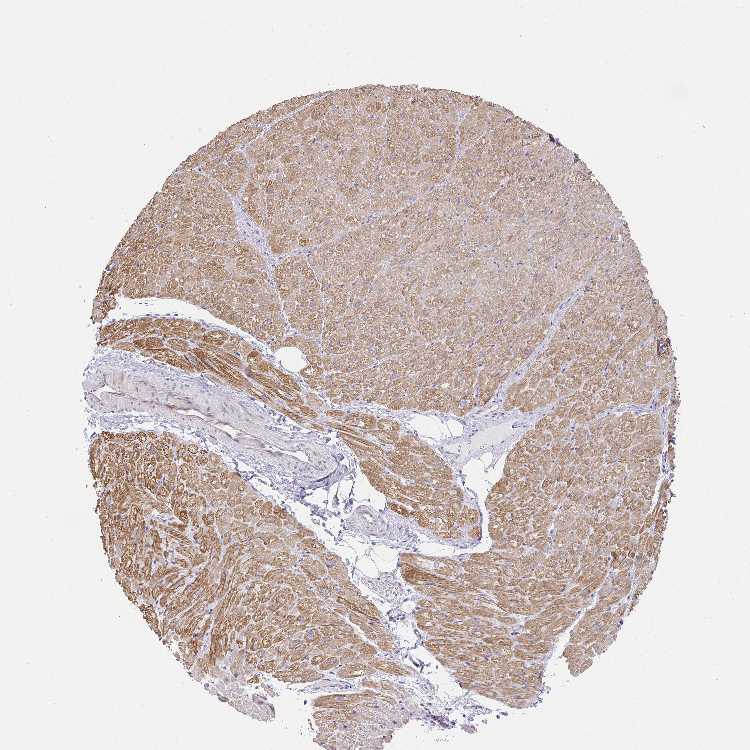

HEART MUSCLE - Antibody stainingi

Antibody staining in the annotated cell types in the current human tissue is reported as not detected, low, medium, or high, based on conventional immunohistochemistry profiling in selected tissues. This score is based on the combination of the staining intensity and fraction of stained cells.

Each image is clickable and will lead to virtual microscopy that enables deeper exploration of all samples and also displays staining intensity scores, fraction scores and subcellular localization as well as patient and tissue information for each sample.

Antibody HPA057688

Cardiomyocytes Medium